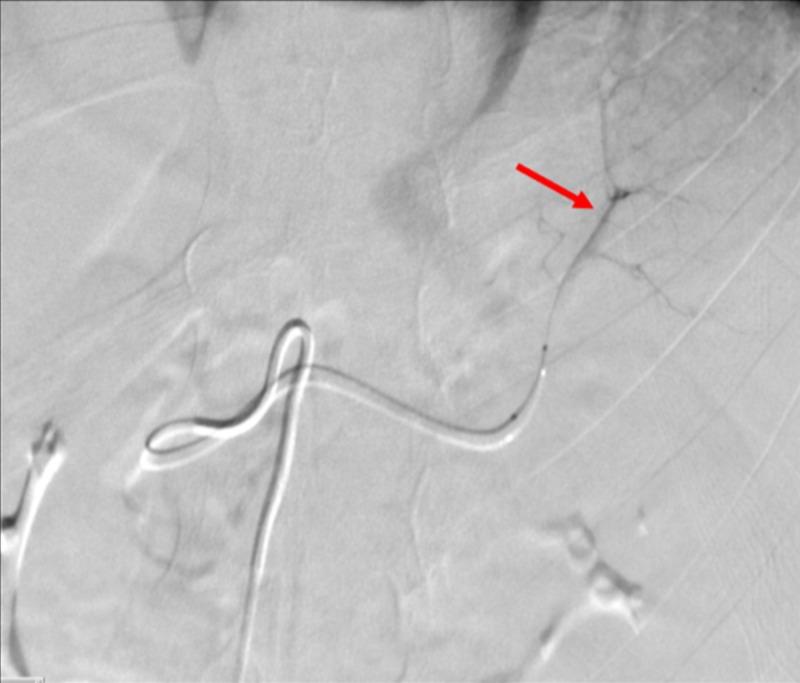

The use of traditionally available intra-arterial devices have historically been designed with the adult patient population in mind. Currently, there are not manufactured devices specifically tailored for use during pediatric interventional procedures, pressuring interventional operators to adapt commonplace and readily available devices for interventional management. Experienced interventional operators understand that pediatric and adult interventions can entail vastly different management, affecting patient care and outcomes. To address the pitfalls in pediatric interventional management, an accredited fellowship specifically for pediatric interventional radiology is available. However, devices must equally evolve with the training available in order to adequately address interventional management of the pediatric patient population. Interventional device innovation can be considered the initial step towards bridging the technical and procedural gaps necessary for refining pediatric intervention. The introduction of steerable microcatheters in interventional radiology has innovated procedural protocols, but has never been documented in pediatric patients until this time.

传统可用的动脉内装置在设计时历来考虑的是成年患者群体。目前,尚无专门为儿科介入手术设计制造的装置,这迫使介入手术操作人员采用常见且容易获得的装置进行介入治疗。经验丰富的介入手术操作人员明白,儿科和成人介入手术在管理上可能有很大差异,会影响患者护理和治疗结果。为解决儿科介入治疗管理中的缺陷,现有专门针对儿科介入放射学的认可进修项目。然而,装置必须与现有的培训同步发展,以便充分应对儿科患者群体的介入治疗管理。介入装置创新可被视为弥合完善儿科介入治疗所需的技术和程序差距的第一步。可操控微导管在介入放射学中的引入革新了手术方案,但在此之前从未有过在儿科患者中的相关记录。